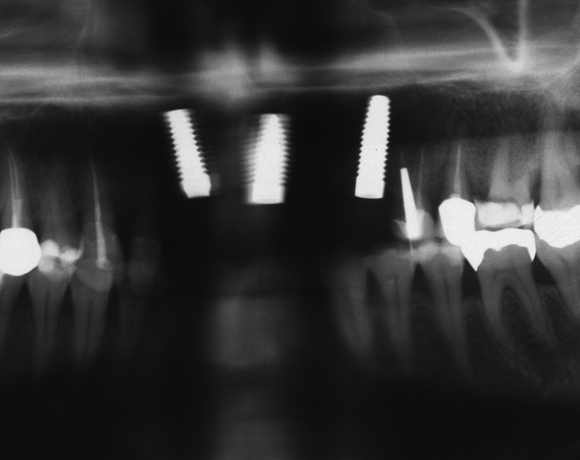

Drei Implantate in der Oberkieferfront

Ein Projekt aus dem Jahr 2011

Im vorliegenden Patientenfall mussten die 11 bis 22 aus parodontalen Gründen extrahiert werden. Die Zähne hatten Lockerungsgrad III, und es bestand ein starker horizontaler Knochenabbau. Das Ergebnis zeigt die Abschlusssituation nach Knochenaufbau und der Insertion von drei Vollkeramikimplantaten.